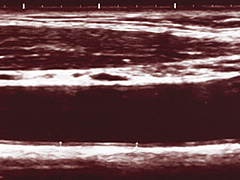

痛みもなく時間もかからない、比較的簡単な検査で動脈硬化の進行度を知る方法があります。それは、「頸動脈エコー(超音波)検査(IMT計測)」という検査です。

頸動脈(けいどうみゃく)といわれる首の血管は、外から簡便に動脈硬化を判定しやすい血管の一つで、この頸動脈の状態を知ることで、全身の血管のおおよその状態が分かるといわれています。血管の硬さや厚みを0.1mm単位で測定し、詰まり具合や動脈硬化の程度を詳しく調べる検査です。正常値は1.0mm以下。1.0mmを超えると脳血管障害と虚血性心疾患の発症率が高くなるといわれています。IMT値は、頸動脈自体が詰まっていないか、あるいはプラークの有無を見ると同時に、全身の動脈硬化の有無を予知する大事な指標です。

画像:頸動脈エコー写真